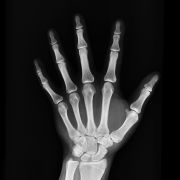

Röntgenuntersuchungen